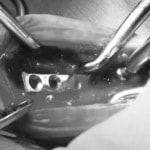

脊髄の減圧、脊柱管の再構築・安定化を目的に、片側椎弓切除術およびMatrixMANDIBLE Plateによる椎体固定を実施しました。

隣接椎体を架橋するようにプレートを設置しました。

術後レントゲン写真